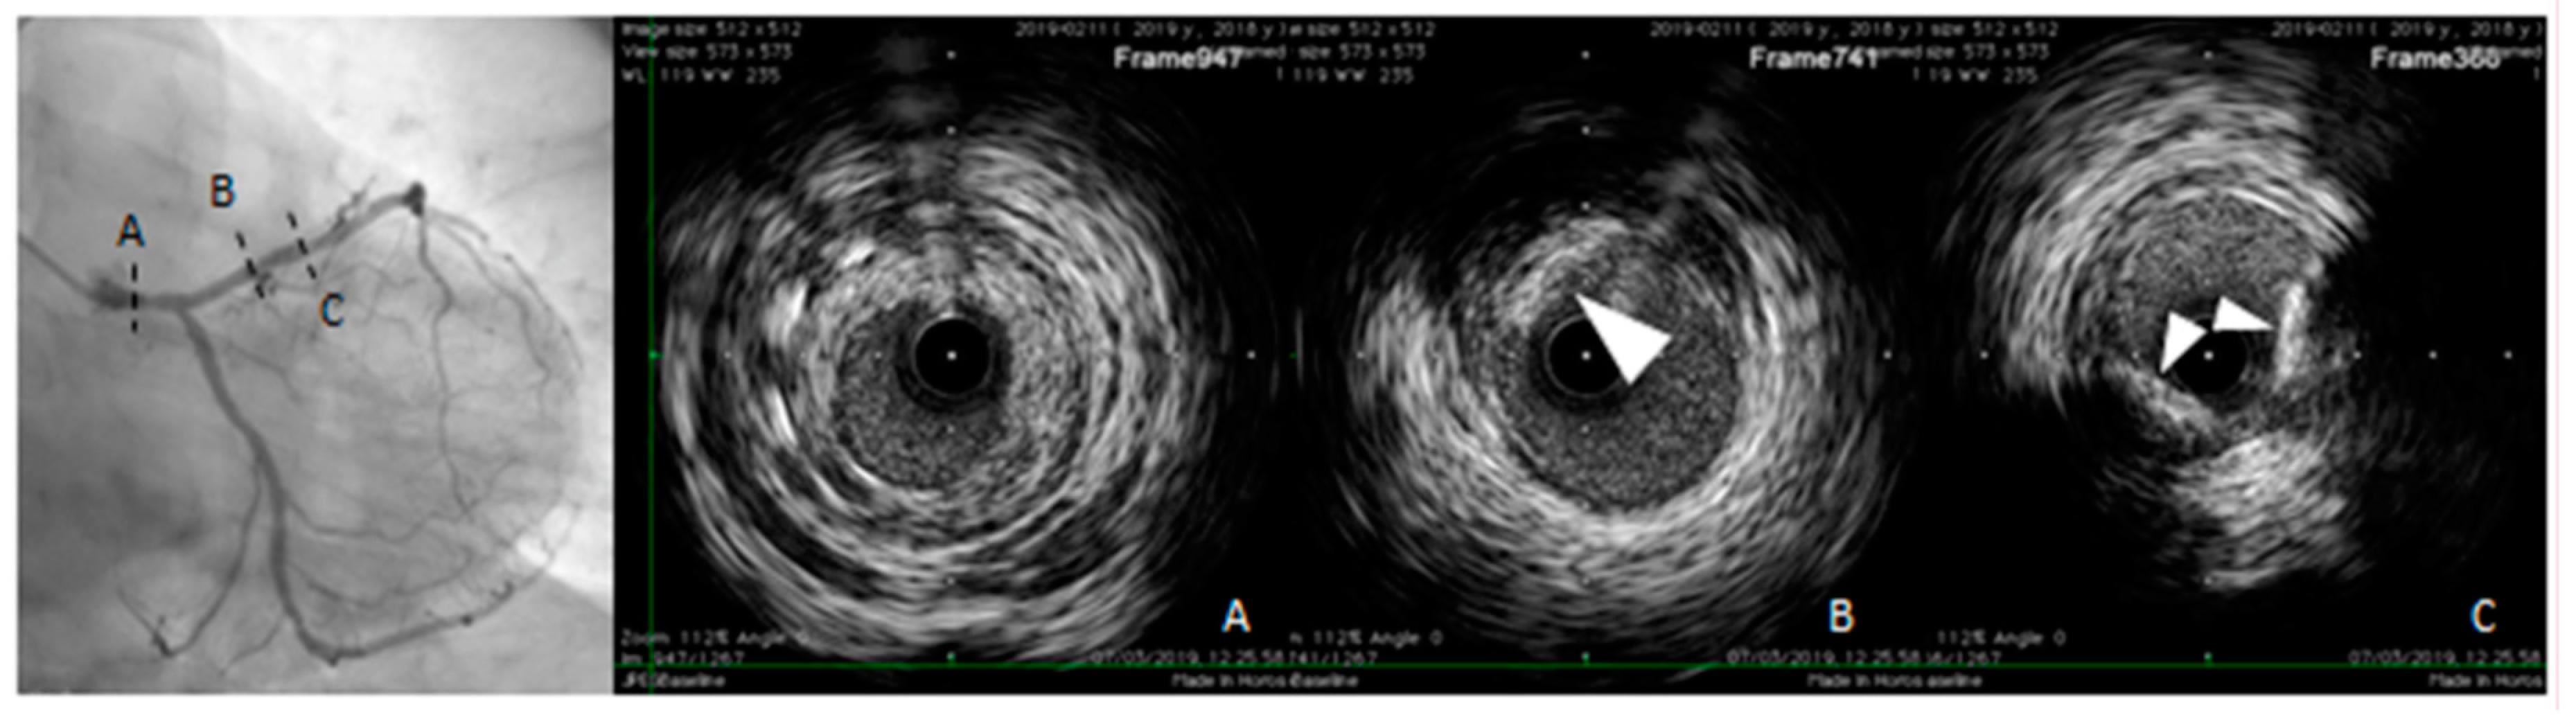

IVUS and OCT allow direct cross-sectional visualization of the coronary wall and are now considered the gold standard for in vivo imaging of coronary calcification [79,100,103]. IVUS imaging is based on ultrasound reflection by coronary calcification and is more sensitive and specific than angiography (Figure 5). Compared to OCT, IVUS has lower spatial resolution and greater penetration depth, thus provide good assessment of the entire arterial wall. However, IVUS cannot penetrate calcium, hence its assessment of plaque calcification is quantitatively expressed as arc (in degrees) and length. Calcified plaques appear echo-dense (hyperechoic) and brighter than the surrounding adventitia. Some grey-scale IVUS signal intensity features have been associated with histological features of plaque instability and high risk of CAD: plaque with ultrasonic attenuation (echo-attenuated plaque), associated with fibroatheroma containing large necrotic core; echo-lucent plaque, containing an intraplaque zone of absent echogenicity, correlated with small necrotic core; spotty calcification and calcified nodule, both associated with acute coronary events [104,105].

Figure 5.

Intravascular ultrasound (IVUS) pull-back in a symptomatic, diabetic female patient with a critical left main stenosis (A, right panel: IVUS frame corresponding to the dotted line A, left panel). Left anterior descending (LAD) presents the diffuse disease with calcific eccentric lesion (triangle arrows B and C right panel, corresponding to the dotted lines B and C left panel). Behind calcifications, shadow does not allow us to obtain complete vessel contours.